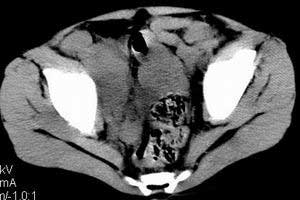

| 患者,男,9岁,因右下腹包块入院,血象不高,不规则发热,常超40度。 平扫: ![]() ![]() ![]() ![]() ![]() ![]() ![]() ![]() ![]() ![]() ![]() ![]() ![]() ![]() ![]() ![]() ![]() ![]() 增强: ![]() ![]() ![]() ![]() ![]() ![]() ![]() ![]() ![]() ![]() ![]() ![]() ![]() ![]() jiajie发言:骶椎右前区不规则软组织肿块,边缘光整,密度均匀,增强后均匀强化,右腹股沟区可见肿大淋巴结,临床有时发热,考虑淋巴瘤,儿童盆腔肿瘤应与神经母细胞瘤和横纹肌肉瘤鉴别。 longzhanghui发言:印象:盆腔右后壁不规则软组织肿块,并向前延伸.似为多个肿块融合,呈中等强化.初步考虑淋巴瘤. 听蝉观竹发言:右侧髂内、外组淋巴结肿大,从其形态和融合的情况看,同意大家意见-----考虑恶性病变,但是9岁男孩还要注意检查睾丸情况,有无隐睾? 常常类似情况是隐睾发生精原细胞瘤淋巴结转移,这个病例也要注意这一点!!! 广东凌发言:大家好,在这里我想说一下个人观点,我建议上传图片的同志能否辛苦一点就是把病史和图片都上传完整一点,比如这个病人的腹膜窗,并且这个病人的肠道的准备也是不怎么好,就从现有的质料看:病灶属于淋巴结肿大当无大的争议,有融合趋势,其内无坏死,边缘强化为主,故考虑:淋巴瘤!建议用腹膜窗看一下和肠道的关系! 阿圣发言:病灶属于淋巴结肿大当无大的争议,有融合趋势,其内无坏死,边缘强化为主,故考虑:淋巴瘤 结果是:淋巴瘤 病例来源:ct762。由宁静致远发布: http://www.radinet.com.cn/forum_view.asp?forum_id=4&view_id=2182 |